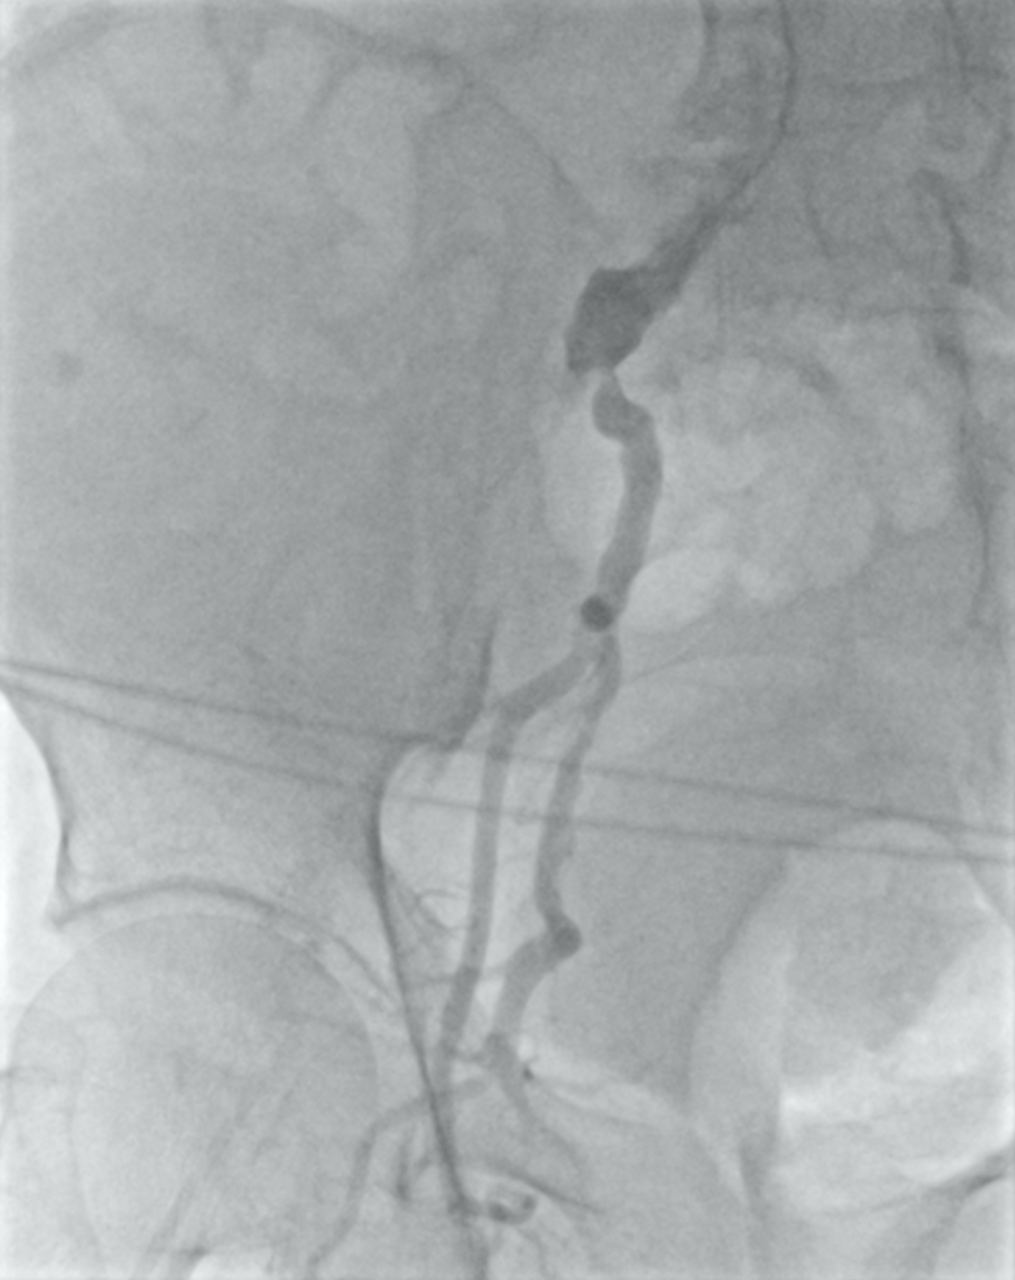

Под местной анестезией выполнена пункция правой плечевой артерии, установлен интродьюсер, проведен диагностический катетер в правую общую подвздошную артерию (ОПА), выполнено антеградное контрастирование ОПА: окклюзия наружной подвздошной артерии от устья, дополнительно выявлен стеноз устья ВПА 90% (рис. 2).

Рисунок 2. Антеградная ангиография доступом через плечевую артерию. Выявлен критический стеноз внутренней подзвдошной артерии. Кровоток по наружной артерии не определяется от устья.